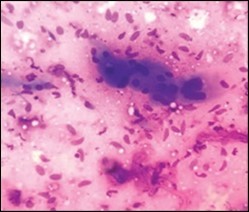

On gross examination, a tan coloured, gritty nodule, confined to the sternocleidomastoid muscle is delineated. Characteristically, smears obtained by fine needle aspiration cytology are composed of bland appearing, plump or normal fibroblasts and proliferating fibroblasts with an admixture of degenerative, atrophic skeletal muscle cells, giant myocytes with several nuclei, scattered, bare, bland nuclei or cells with fragmented, wispy cytoplasm and parallel aggregates of fibroblasts. The background is clear and devoid of cellular or nuclear debris. Sheets of spindle-shaped fibroblasts, atrophic muscle fibres and regenerating, multinucleated muscle giant cells are intermingled with the fibroblastic component 5, 6.

Figure 4.Fine needle aspiration cytology of fibromatosis colli delineating aggregates of plump, spindle-shaped cells admixed with fibroblasts, fibro-connective tissue fragments and intermingled red cell extravasation 11